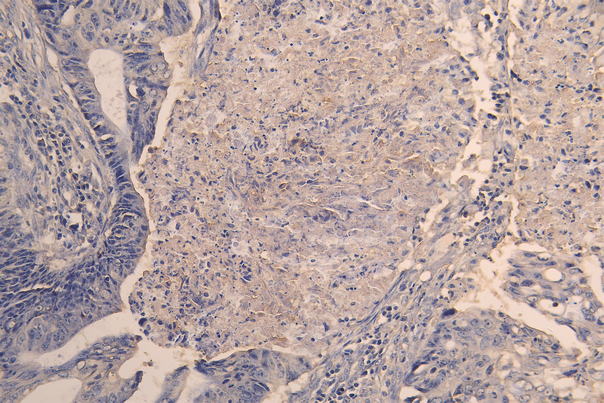

IHC image of CSB-RA623829MA1HU diluted at 1:200 and staining in paraffin-embedded human colon cancer performed on a Leica BondTM system. After dewaxing and hydration, antigen retrieval was mediated by high pressure in a citrate buffer (pH 6.0). Section was blocked with 10% normal goat serum 30min at RT. Then primary antibody (1% BSA) was incubated at 4°C overnight. The primary is detected by a Goat anti-human polymer IgG labeled by HRP and visualized using 0.05% DAB.